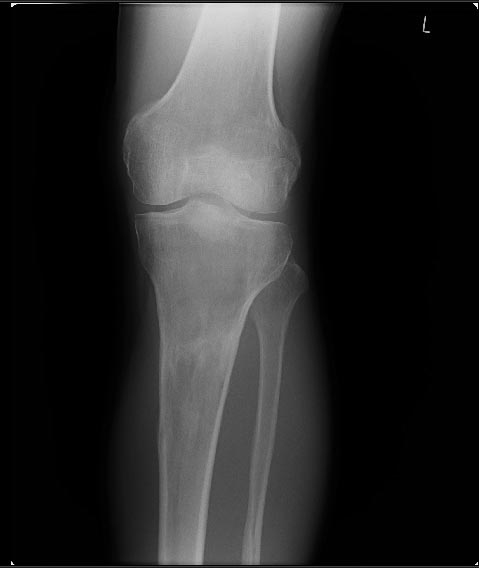

В настоящий момент жалобы на ограничение сгибания в коленных суставах. Снимки прилагаются.

Что можно сделать? У кого есть опыт лечения patella baja?

Возможно( ни в чем не уверен) но причина ,что пошли высоковато ,через бугристось на голенях и собственная связка так же вытягивалась, смещая надколенник вниз? На рентгене же связки оссифицированы,больше справа.

Чего только на коленках не оперировал,а вот низкое стояние как-то не доводилось. А проблема ведь ни в самом низком стоянии надколенника,а скорее в ригидности собственной связки.(Хочется предложить вентрально-просимальное смещение бугристости с тендораффией сухжилия 4-х главой мышцы и рассечением retinaculum extenzorum и возможно и гемопателляэктомией) Но.. Перед тем как давать советы неплохо бы посмотреть снимки феморопателлярного сустава- по Сеттегасту,Кнудсену итд. Исчерпаны ли все возможности реабилитации?

Высылаю снимки, свидетельствующие, что уровень остеотомий вроде как обычный, повторюсь, подобного осложнения после удлинения я не встречал ни у себя ни

в литературе. Сейчас на первое место встает вопрос как помочь данному пациенту. У кого есть опыт лечения patella baja?

Остеотомия высокая, почти на уровне бугристости, так что область прикрепления связки надколенника близко. Я бы делал на 2-3 см ниже. Удлинять на уровне диафиза стало особенно актуально в свете смены аппарата на гвоздь по окончании удлинения.

Лечение - проксимальное перемещение бугристости с частью tibial crest. Как пишут в COO -c"Tibial tubercle osteotomy was originally described for quadriceps relaxation during primary or revision TKA (Fig.7-84). Whiteside and Ohl recommended elevation of an 8- to 10-cm segment of the bone that includes the tibial tubercle and a portion of the anterior crest of the tibia, leaving the anterior compartment musculature attached to the fragment laterally for vascularity. The tubercle can be advanced proximally for patella baja or if the joint line is elevated significantly (Fig. 7-85). They described reattaching the tubercle with multiple wires; other authors have advocated using screws. With secure fixation, passive range of motion can be begun early, but active extension still must be delayed."